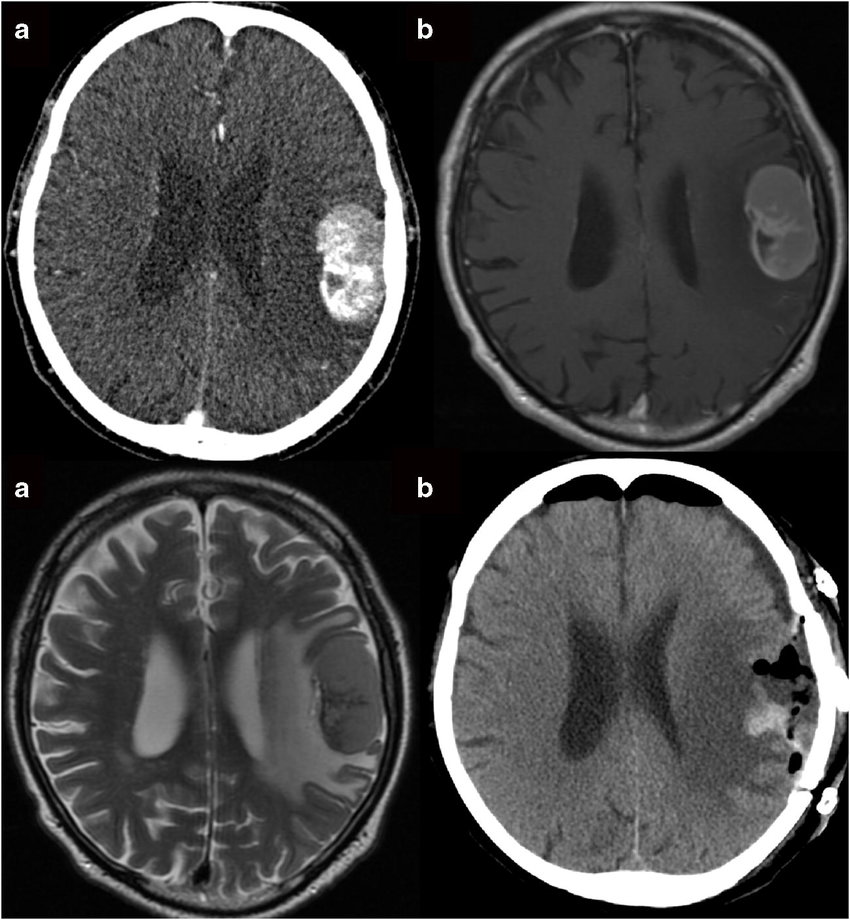

囊性脑膜瘤是什么?囊性脑膜瘤是一种不常见的脑膜瘤,肿块的囊性/实性成分的影像学表现和位置可能造成诊断上的两难。我们报告了一例80岁的左手男性患者,其表现为反复发作的局...

什么是多发脑膜瘤?是恶性的么?诊断多发性脑膜瘤需符合以下几点:患者存在一个以上的脑膜瘤;虽然对于脑膜瘤来说,其处理原则是手术完全切除肿瘤,但对于多发性脑膜瘤,不可...